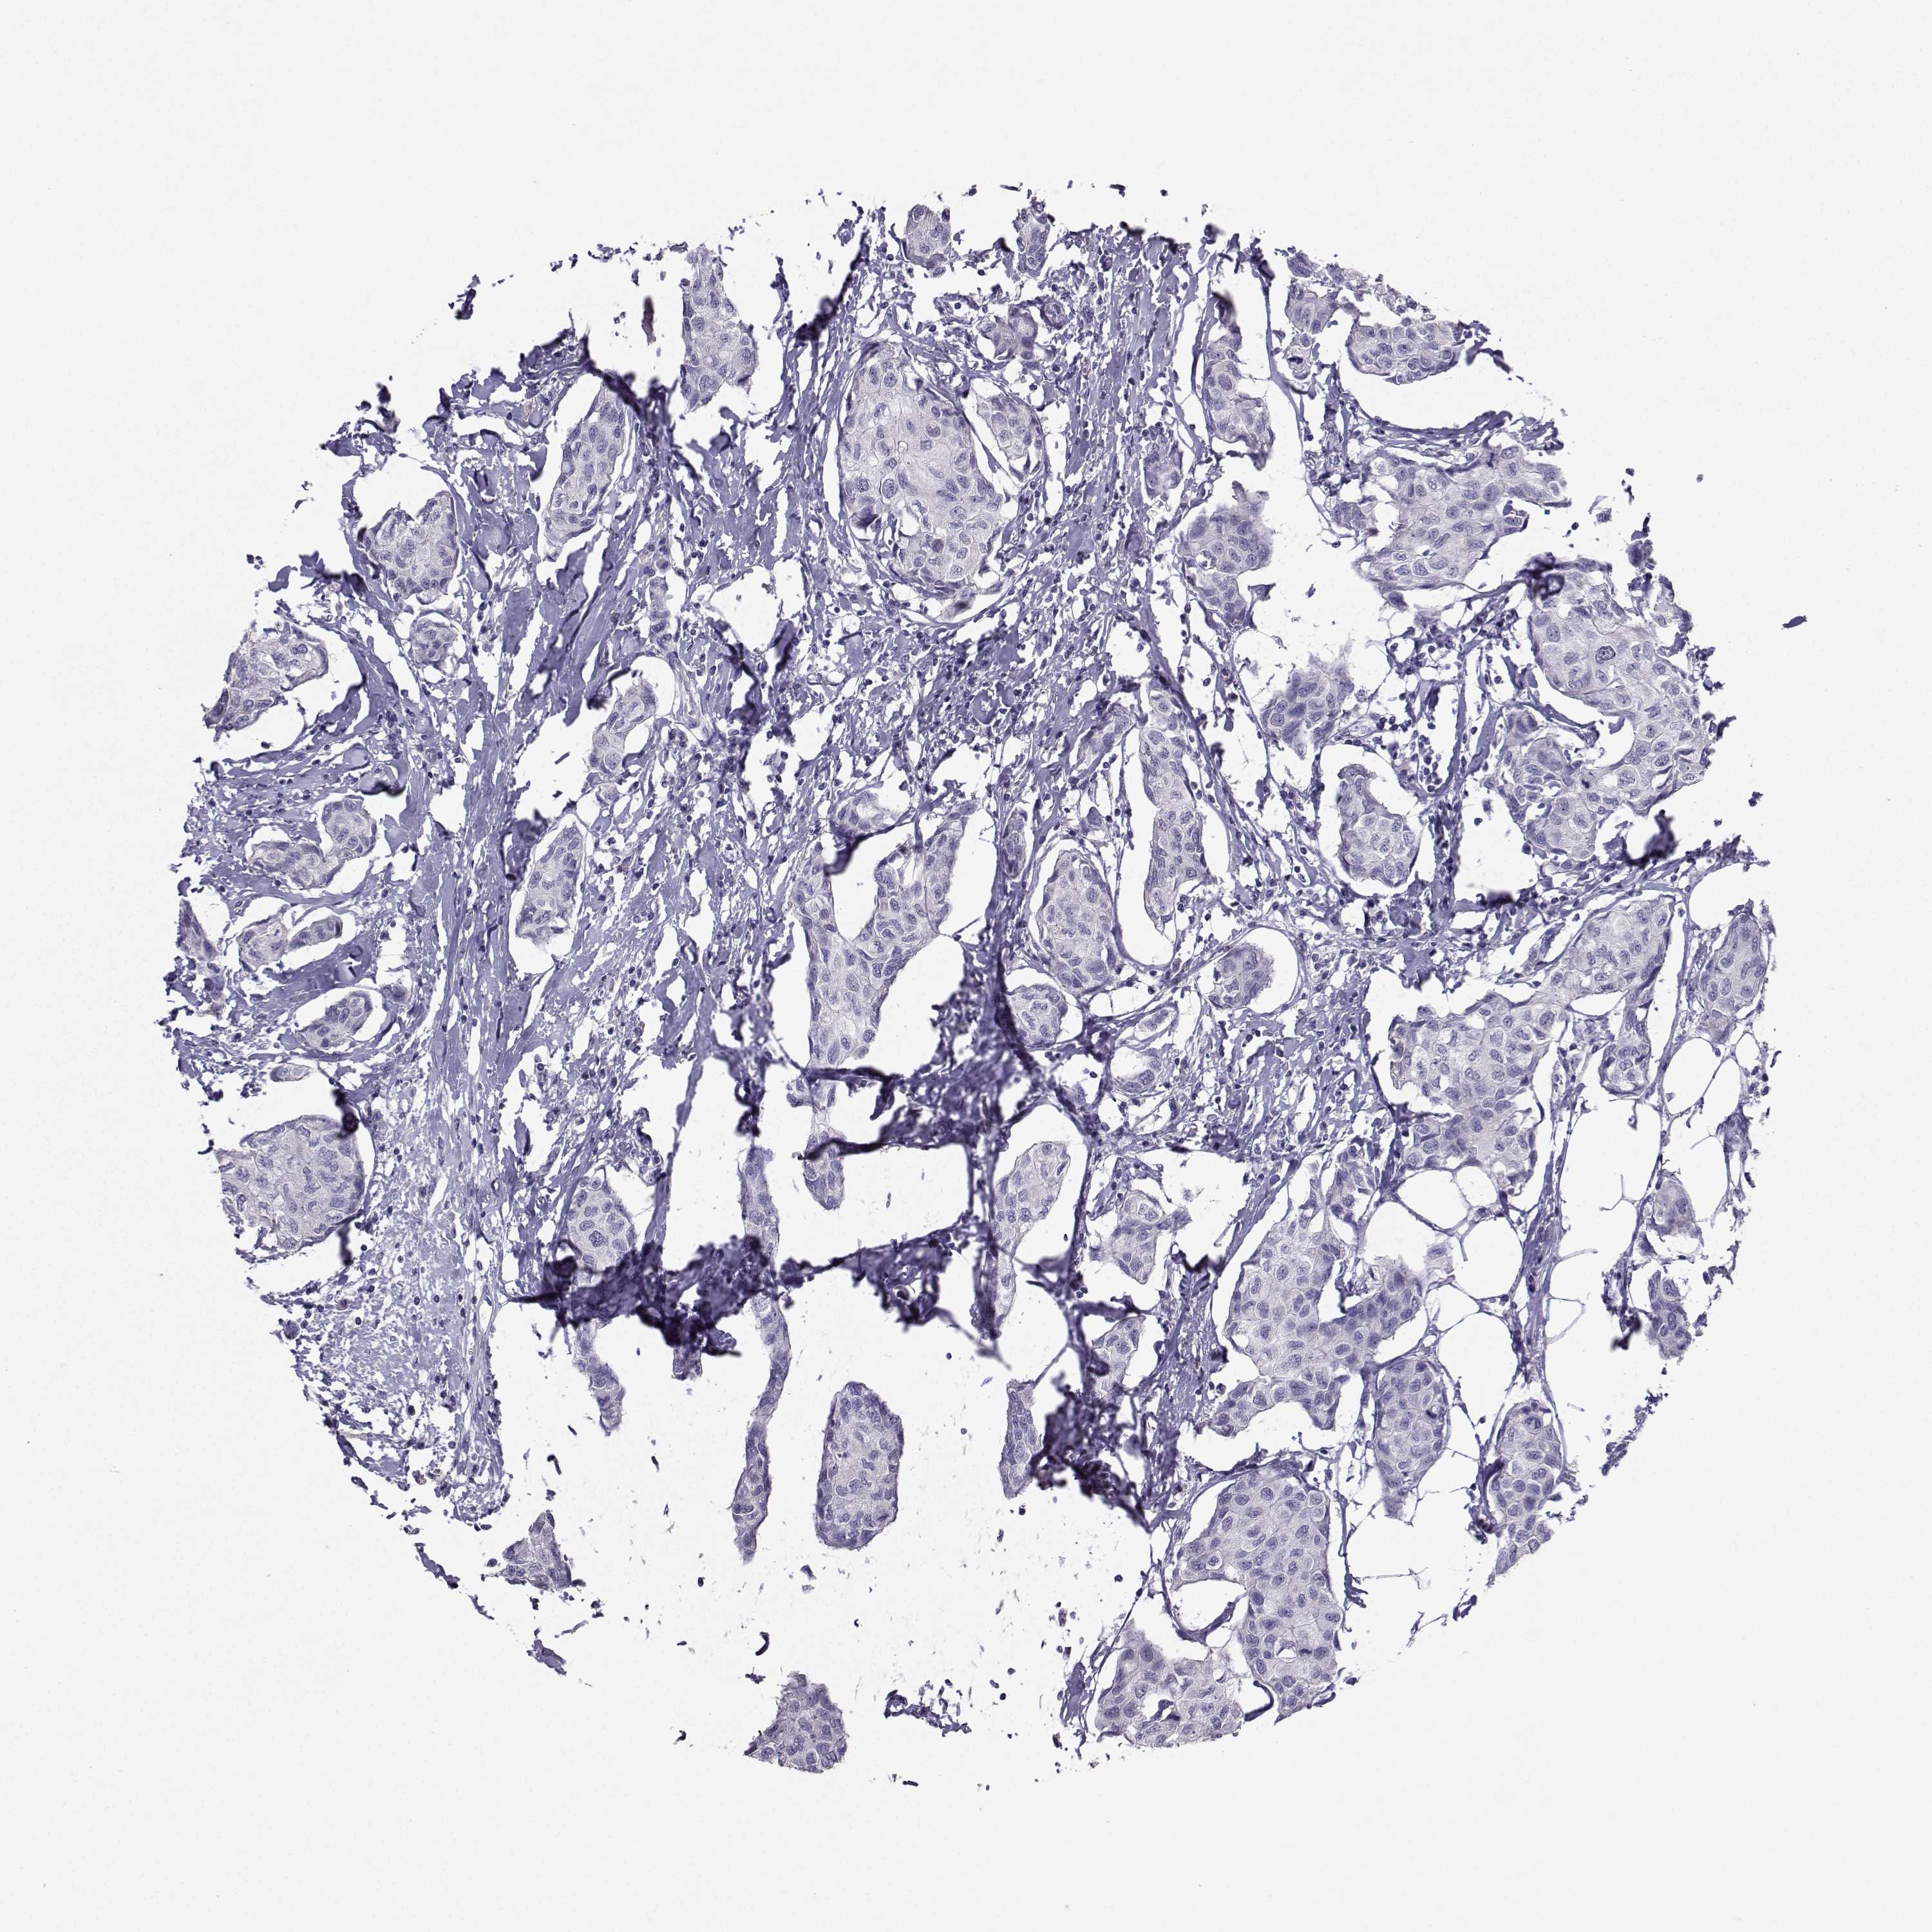

Breast cancer

Human cancer